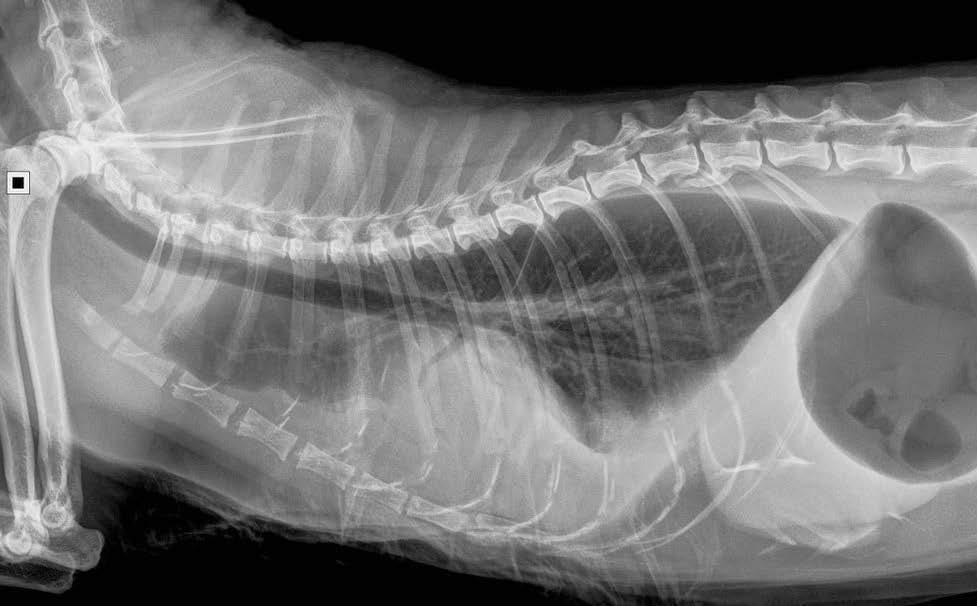

Le pyothorax chez le chien et le chat

Le pyothorax, aussi appelé empyème pleural, est défini par l'accumulation d'un exsudat purulent septique dans la cavité pleurale (CP). Un processus infectieux, bactérien dans la grande majorité des cas, provoque une augmentation de la perméabilité des ca...